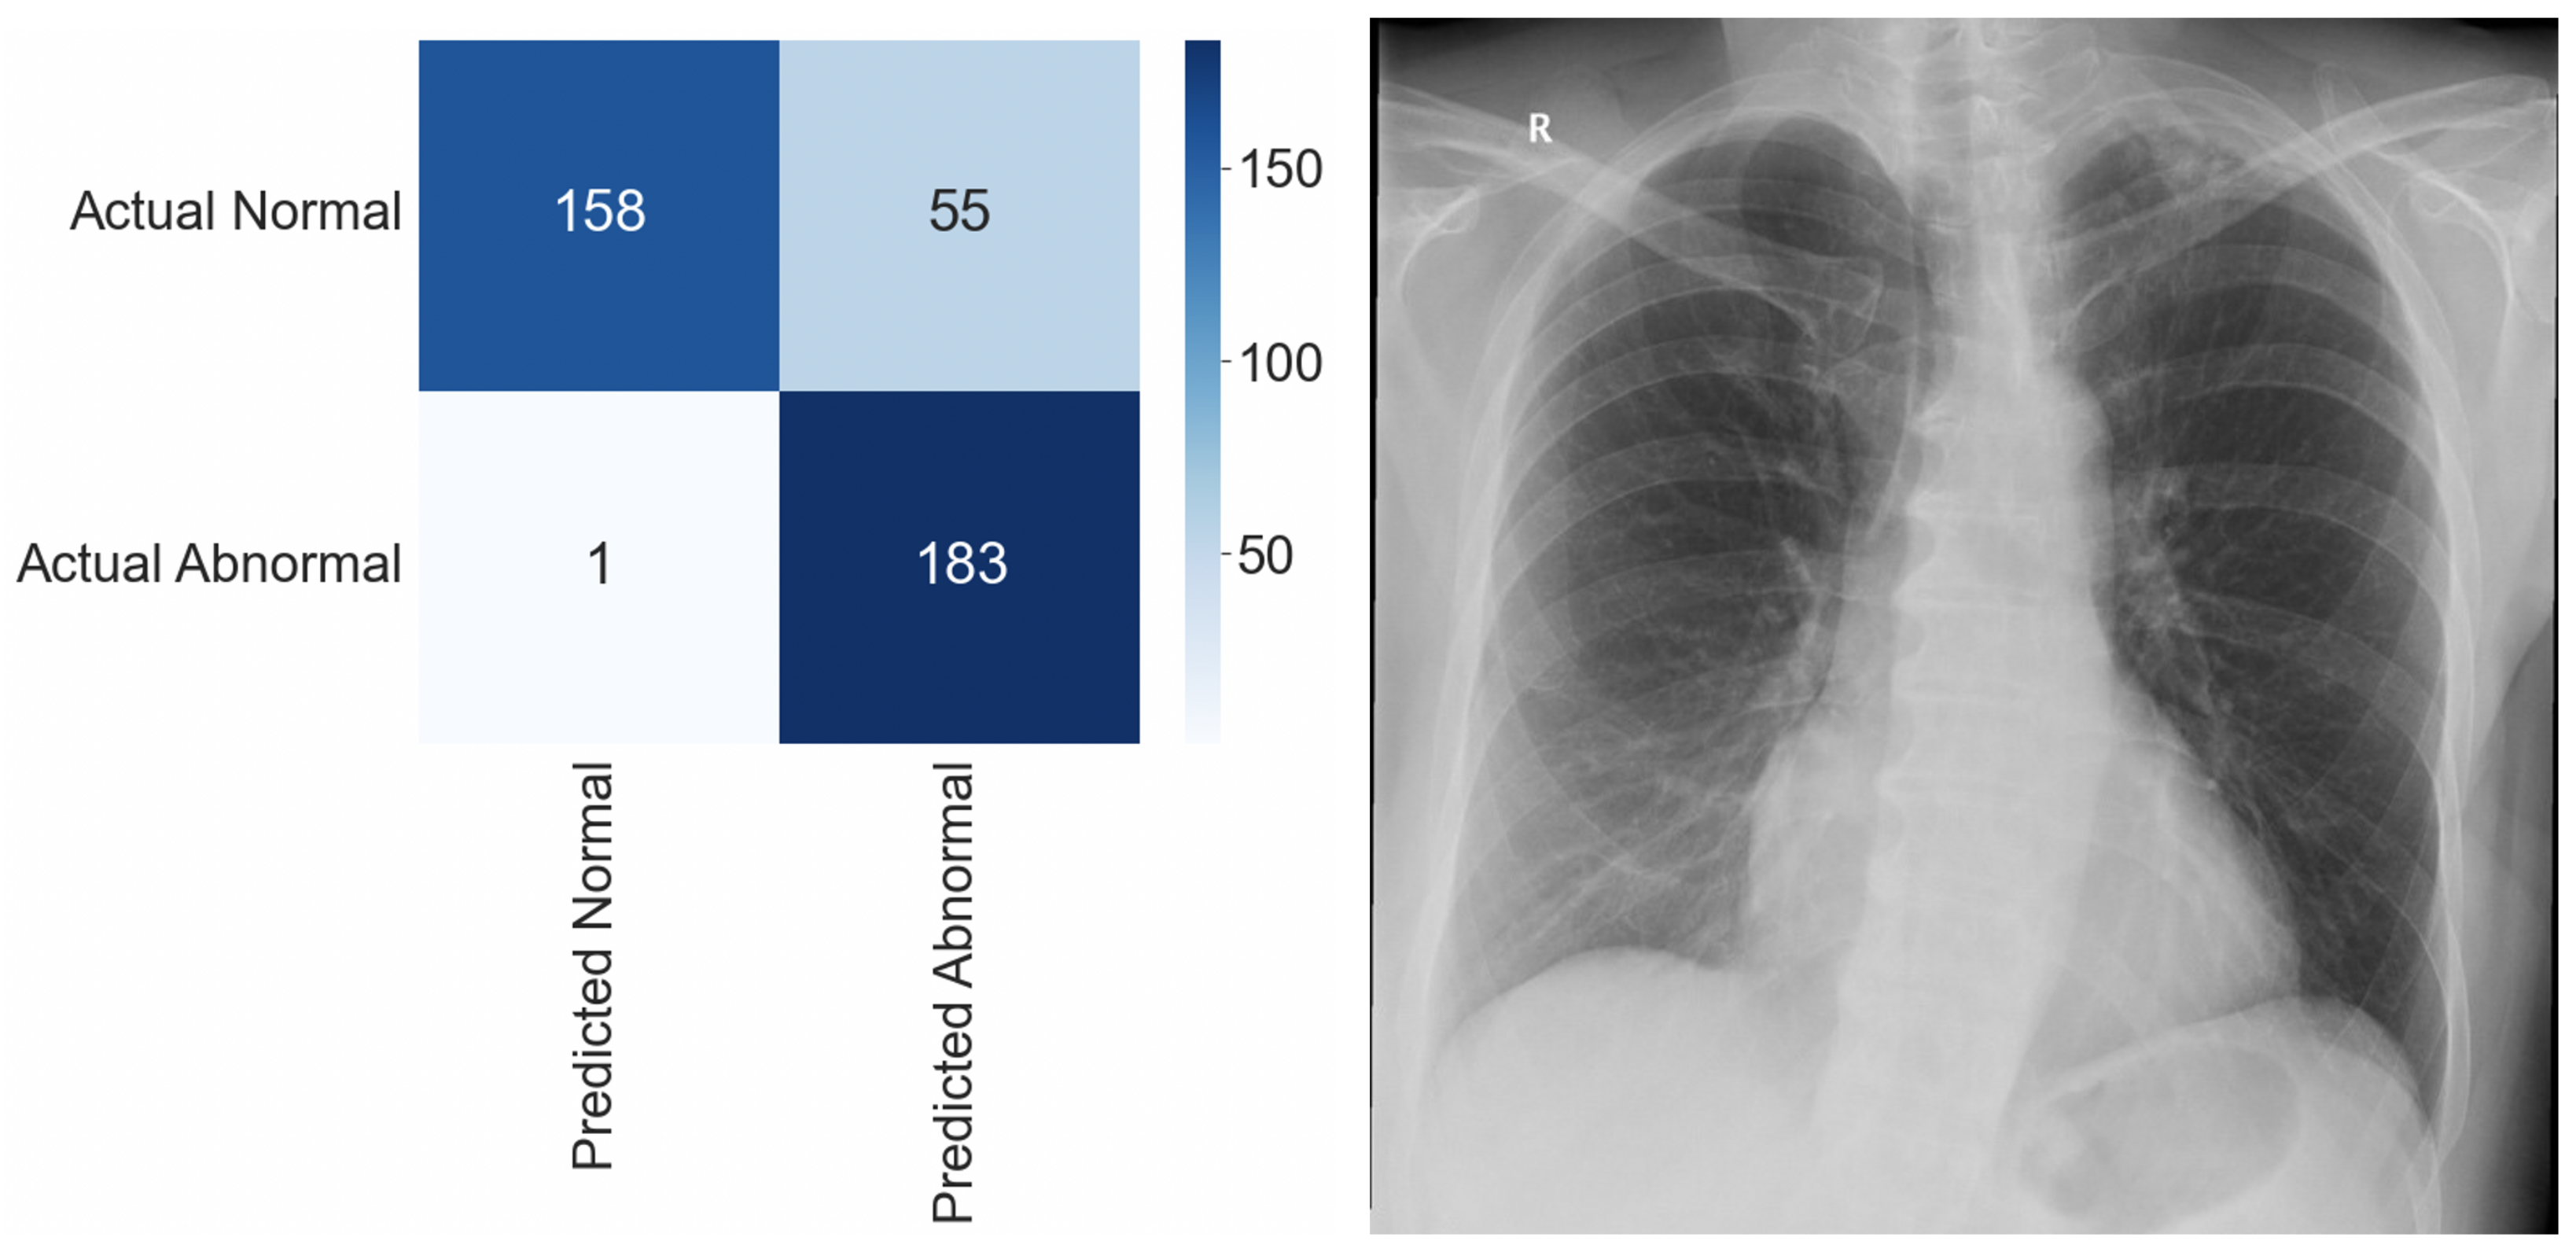

For the initial internal test, we used 397 CXRs that were not observed during the model training. Selected images were retrospectively assessed by three independent radiologists. The ground truth was determined by 100% agreement. The results of the internal test are shown in Table 1. Figure 2 shows an image involving a rib fracture that DLAD incorrectly classified as a scan without any abnormality.

Figure 2.

Confusion matrix and a false negative image that DLAD incorrectly classified as a true negative during the internal test. The CXR scan in high quality can be found in the Appendix A (Figure A1).

Of the selected images, 213 (53.65%) were reported as normal and 184 (46.35%) as abnormal. DLAD software correctly interpreted 338 images (85.1%), with only one image resolving in a false negative outcome (FNR = 0.0054). A higher false positive rate (FPR = 0.2582) is an expected occurrence. Considering that DLAD software is intended to serve as a decision support system, this outcome is considered rather desirable.